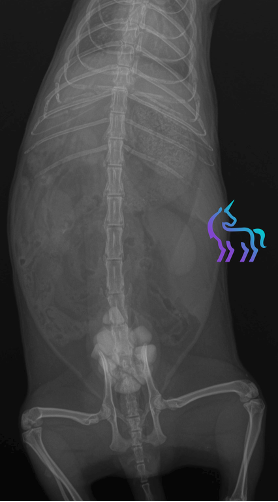

Radiographie

La radiographie abdominale met en évidence la présence de multiples calculs intravésicaux, confirmant l’origine obstructive des troubles urinaires.